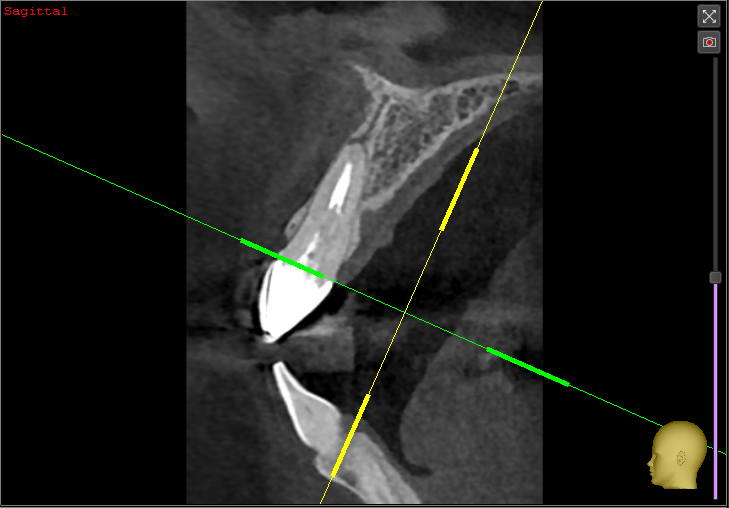

Lex2023 Опубликовано 19 июня, 2023 Автор Поделиться Опубликовано 19 июня, 2023 @IvanK Здравствуйте. Сегодня сделал 3д снимок, сказали все хорошо (воспаления нет, канал запломбирован хорошо, сам корень без трещин и т.п), соседние зубы тоже в отличном состоянии , но боль не проходит.Коронку снимать смысла нет говорят. Попросил результат сканирования, скинули вот это.Если можете, посмотрите пожалуйста, не знаю уже к кому обращаться. 789686638_20230619-115700-142_.zip Ссылка на комментарий

АнтонТЛТ Опубликовано 20 июня, 2023 Поделиться Опубликовано 20 июня, 2023 Канал не до конца запломбирован Ссылка на комментарий

Lex2023 Опубликовано 21 июня, 2023 Автор Поделиться Опубликовано 21 июня, 2023 (изменено) 20.06.2023 в 14:09, АнтонТЛТ сказал: Канал не до конца запломбирован @АнтонТЛТ Может можно медикаментозно это вылечить, врач видел что не до конца запломбирован канал, но сказал что из-за него не может болеть, пломбировали задолго до установки коронки, больше 10-ти лет точно прошло. А если и перелечивать реально эту же коронку сохранить? Изменено 21 июня, 2023 пользователем Lex2023 Ссылка на комментарий